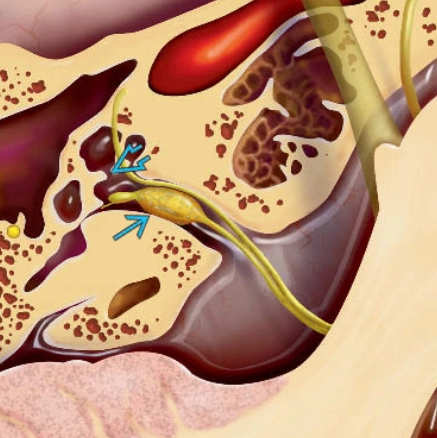

U bao dây thần kinh tiền đình (Vestibular schwannoma - VS)

Phân loại Koos cho u schwannoma tiền đình - Koos classification of vestibular schwannomas